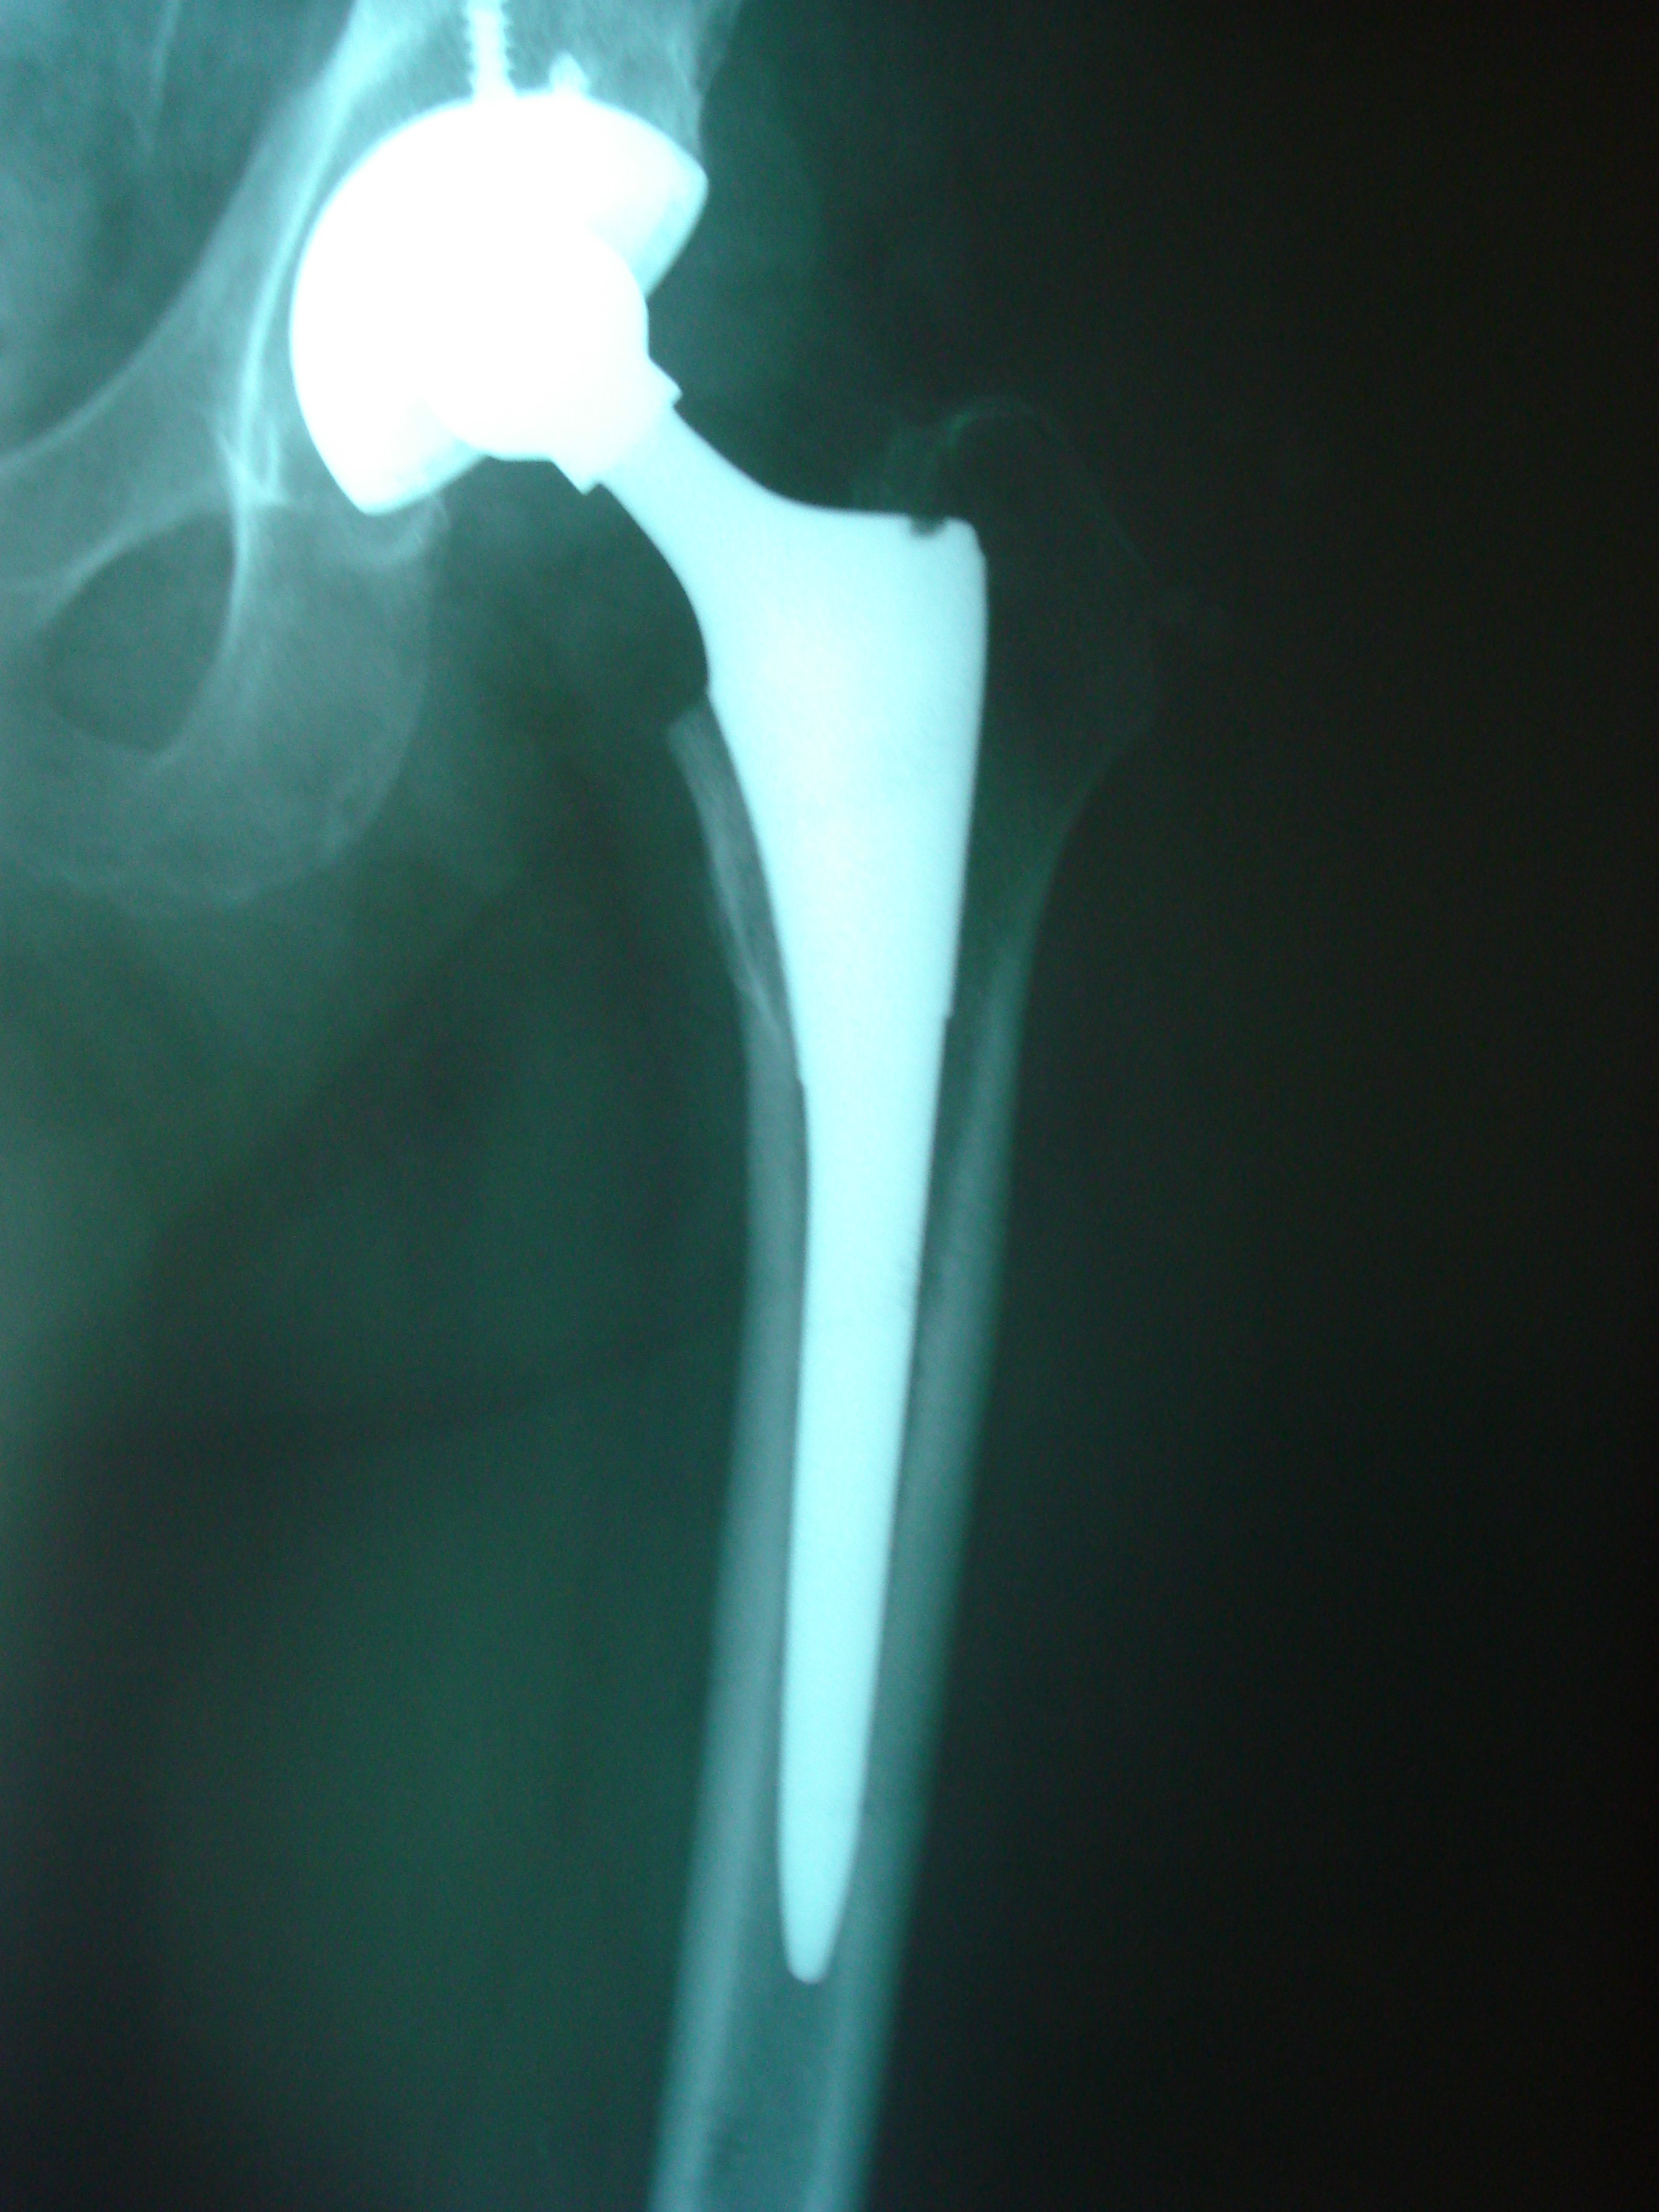

Geç dönemde eklem bozulduğunda kalça protezi ile tedavi

Olgun dönemde kalça sorunları

• Kalça kırıkları

• Kalça artrozu

• Romatizmal hastalıklara bağlı kalça tutulumu